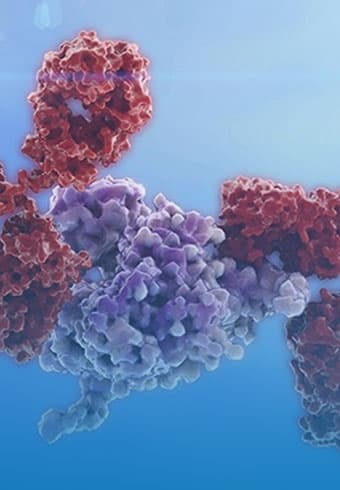

PROTAC Targeted Protein Degradation(TPD)Platform

Competitive Advantages of Hinova PROTAC Platform